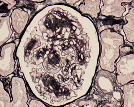

Histoquímica

Técnica que, através de reações químicas, permite evidenciar determinados constituintes celulares, depósitos exógenos e microorganismos.